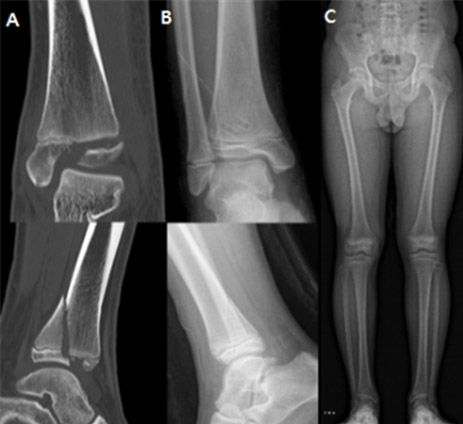

- ▲ A. 발목 성장판 골절이 발생한 12세 남아 환자의 모습, B. 생체흡수성 나사를 이용해 골절 부위를 고정하는 수술적 치료(고정술)를 시행한 모습, C. 수술 2년 후 성장판 손상 없이 회복된 모습, 성장판 골절로 인해 발생할 수 있는 변형이나 다리 길이 차이 등이 나타나지 않은 것을 확인할 수 있다. /사진 제공=분당서울대병원

연구팀은 발목 성장판 골절로 수술을 받은 15세 이하의 환아 67명을 대상으로, 금속 나사(40명)와 생체흡수성 나사(27명)를 이용한 수술 결과를 비교했다. 지금까지 성인 골절 환자를 대상으로 생체흡수성 나사를 이용한 수술 결과는 보고된 바 있으나, 소아 환자를 대상으로는 관련 연구가 거의 이뤄지지 않았다.

연구 결과, 두 군 모두에서 성장판 손상 비율, 수술 시간, 수술 후 발목 기능이 우수했으며, 수술 후 감염, 상처 등 합병증 또한 없어 유의미한 차이 없이 동등한 치료 결과를 보였다. 하지만 생체흡수성 나사를 이용한 수술을 받은 환자군의 평균 입원 기간은 2.6일로, 금속 나사를 이용한 수술을 받은 환자군(5.2일)보다 절반가량 짧아 시간적 부담이 적은 것으로 나타났다.